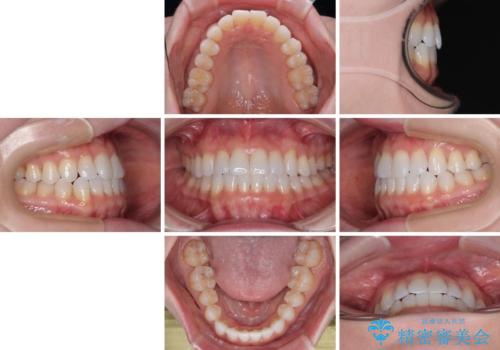

- 上下前歯の叢生を気にして来院された患者様です。

インビザラインでの治療を希望されていて、デコボコの程度が中等度であり、安価なパッケージにて対応可能と判断されたため、インビザライン・モデレートを用いて矯正治療を行うこととしました。

インビザライン・モデレートは、製作できるアライナーの枚数に制限があるため、移動可能な量に限りがあるものの、インビザライン・ライトよりも枚数が多いため、幅広い症例に対応可能です。